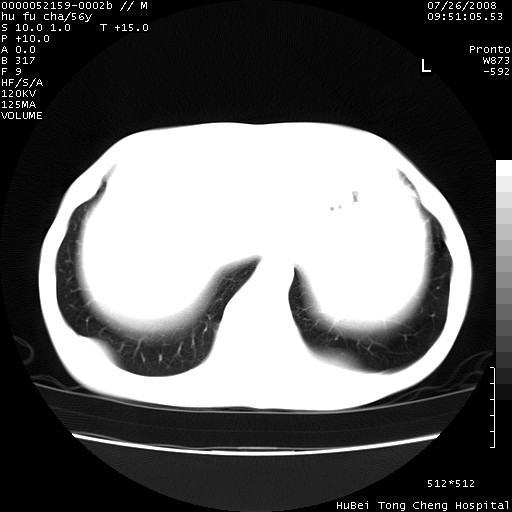

以下是引用zsl6918在2008-8-25 22:47:00的发言:[br]胸骨,胸椎及肋骨均可见多发转移表现,肝内低密度结节不除外转移。原发灶可能在右肺。双侧可见支扩表现。